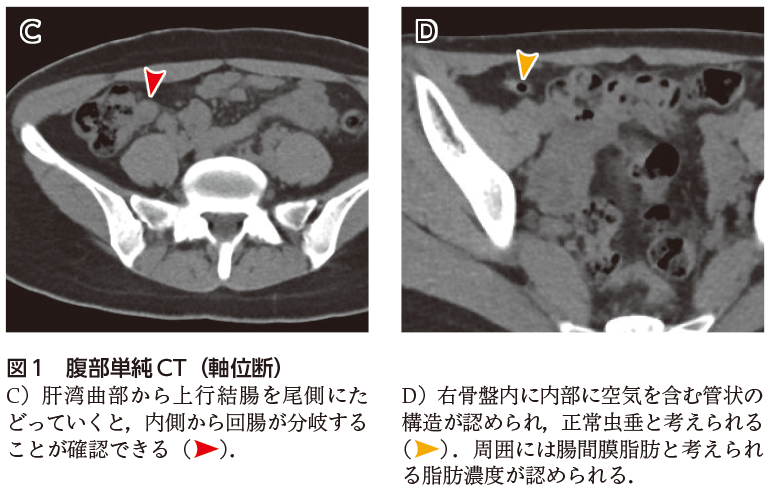

画像診断cafe 虫垂炎-虫垂炎17例中16例(941%)に手術が施行され, 病理組織学的診断は,壊疽性虫垂炎11例,蜂窩織炎 性虫垂炎3例,慢性虫垂炎2例であった(表2)。壊 疽性虫垂炎では,横径6mm以上の虫垂腫大が909%, 虫垂壁の全周性の同定が1%,虫垂壁の部分的欠損虫垂炎においては,画像診断の役割は非常に大きい. 加えて,虫垂炎の診断が得られた場合,さらに虫垂 の炎症の進行を画像的に評価することで,その治療 方針に大きく寄与することとなる. 当施設ではerで小児科医のトリアージ・初期評

虫垂炎とct画像診断のポイントについて動画でまとめました。 以下についてまとめました。 ・虫垂炎とは?場所は? ・虫垂炎の原因は? ・虫垂炎のct画像診断のポイントとは? 1,虫垂自体の炎症所見 2,周囲への炎症波及所見 3,穿孔所見 参考になれば嬉しいです。虫垂の解剖の理解に重点をおいた虫垂炎画像診断のためのスライドです. 初期研修医や医学生,自信を持って虫垂炎を除外・診断したい若手医師のために作成しました.まずは虫垂炎の診断に自信をつけましょう. *** 以前のスライドに大幅追記・修正したものになります.画像検査の読み方 虫垂炎 画像読影の基本 急性虫垂炎の画像診断は,超音波検査や ct検査が選択されることが多い。超音波検 査は肥満患者や腸管ガスが貯留している患者 では診断が困難となり,ct検査では内臓脂 肪が少ない患者やイレウスを合併した患者で